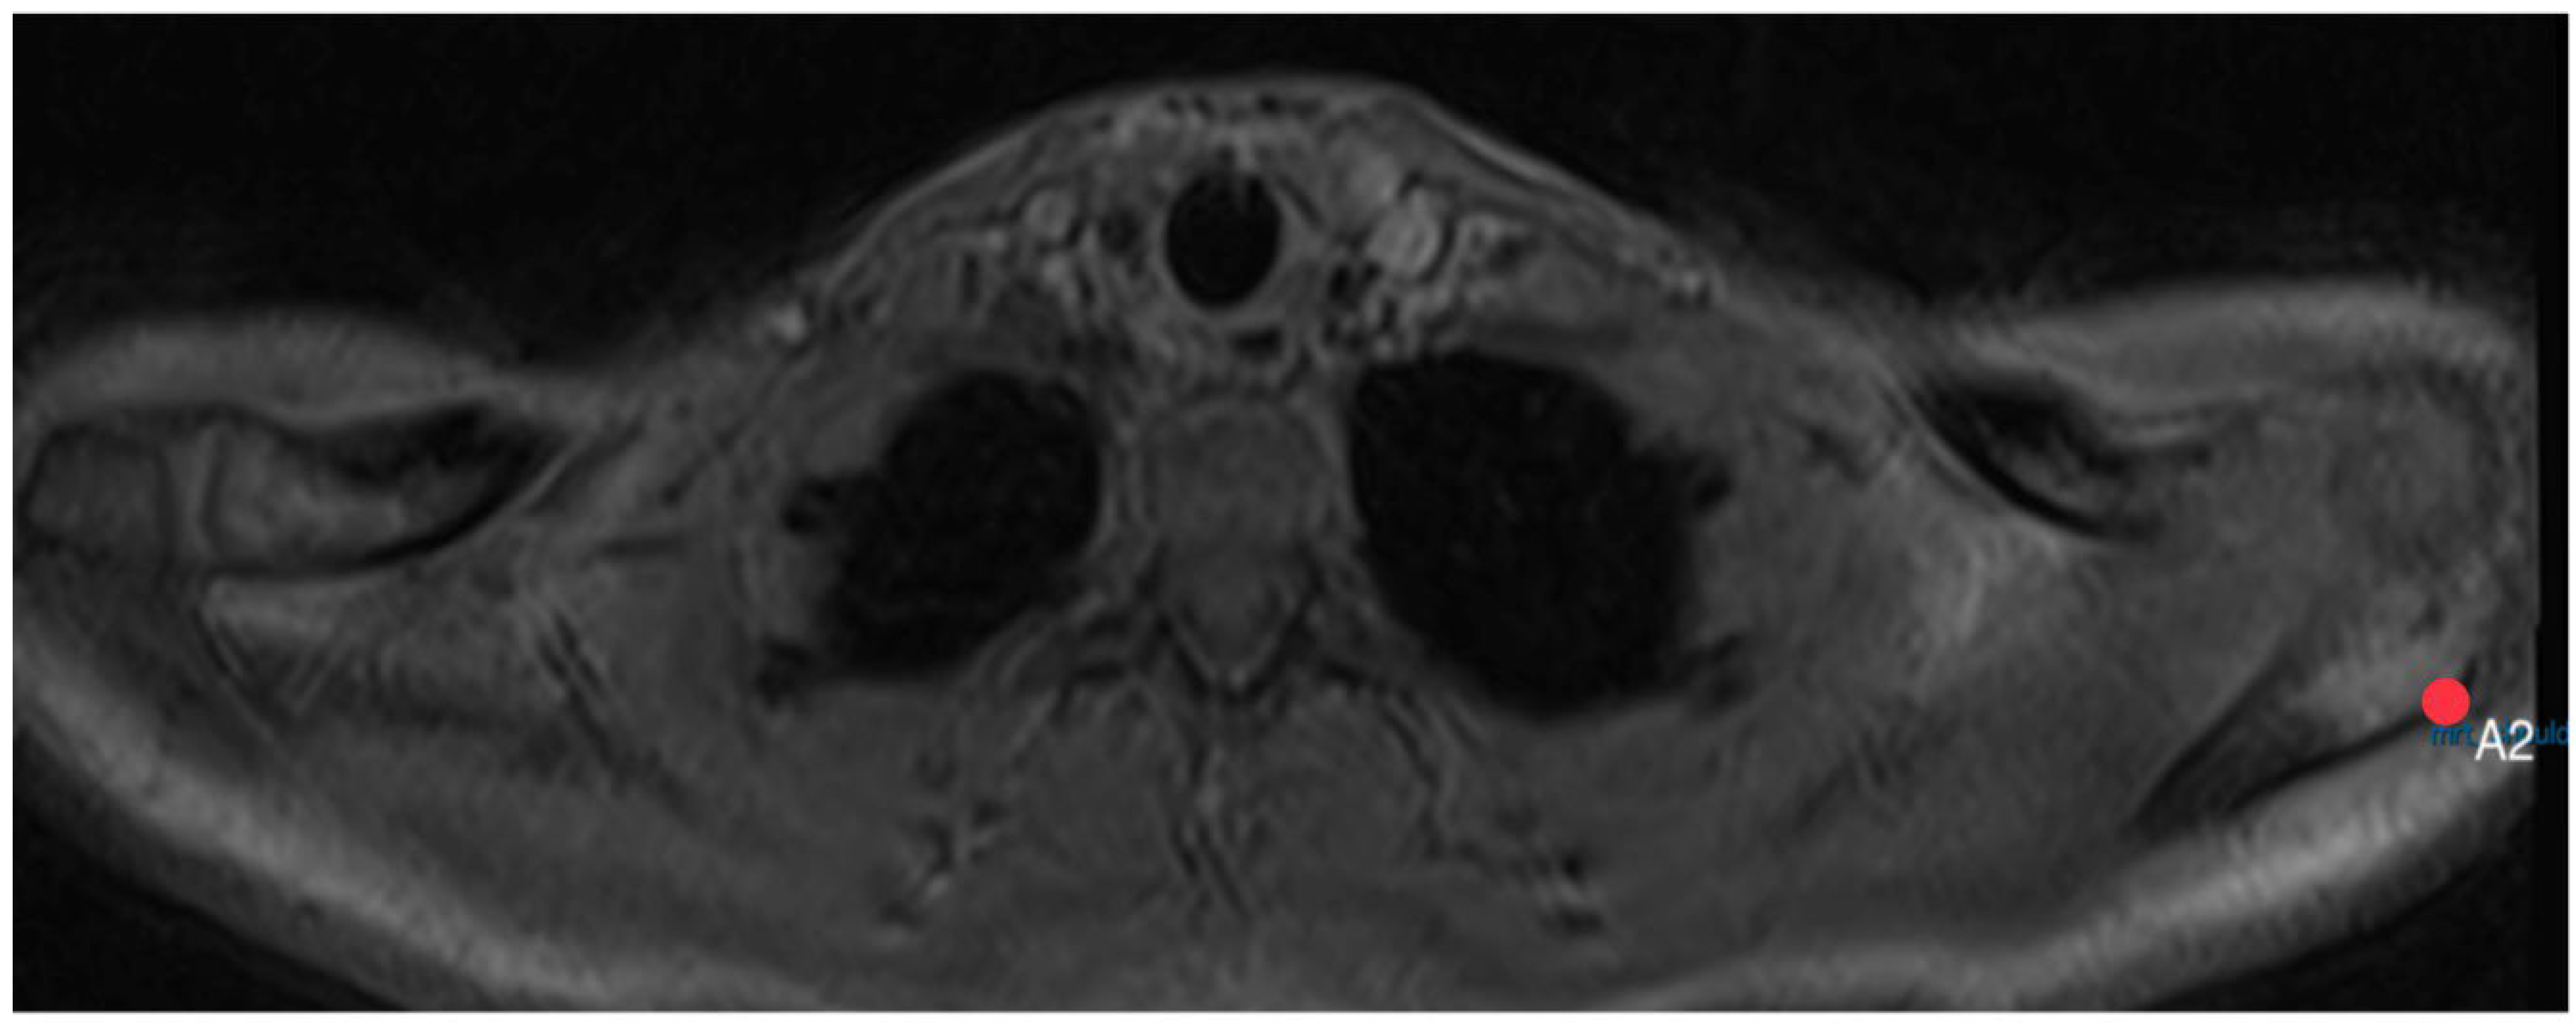

2.5. Acromion Slope (Figure 10)